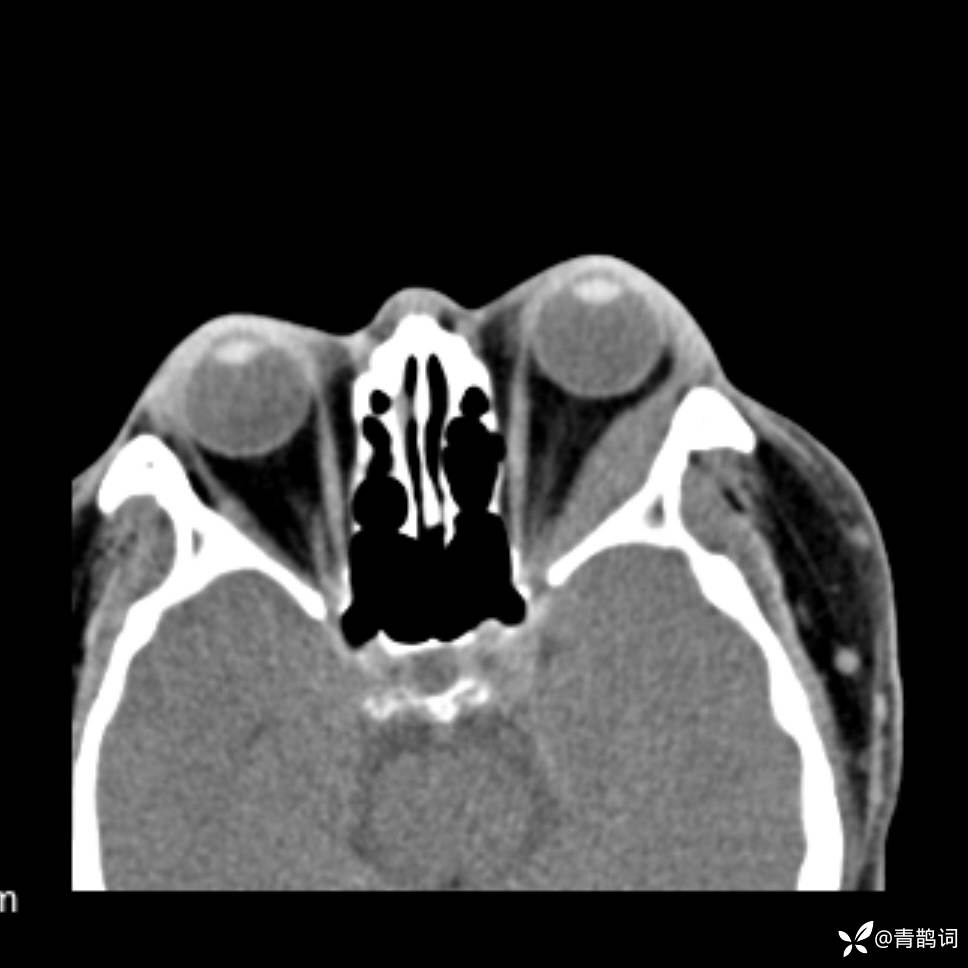

患者年龄:30岁。

患者性别:男。

简要病史:左颜面部肿胀2年,反复咳嗽咳痰,逐渐加重。

辅助检查

结合病史及影像学表现,期待评论区各位老师各抒己见~